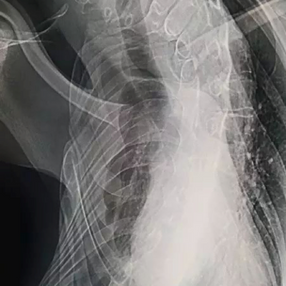

The chest wall was severely deformed, with the left side protruding both forward and backward, and the development of the right side halted with pronounced scoliosis. Meanwhile, the heart and lungs were severely compressed.